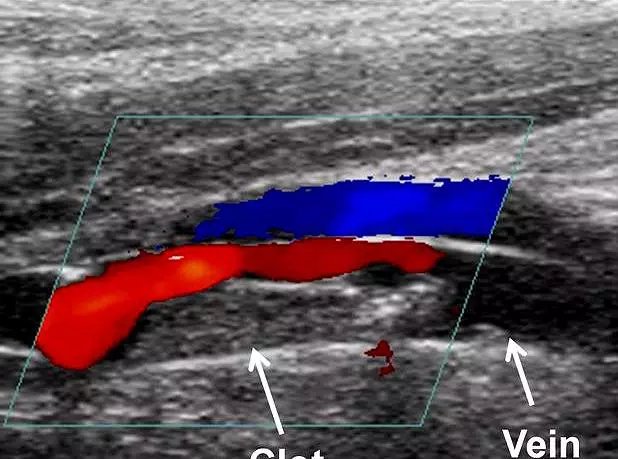

静脉血栓形成也会导致足部的肿痛。

静脉系统也是这样,当静脉系统出现了血栓,动脉仍然会持续的供血,那么静脉内的压力会越来越大,就将会向组织内有渗出,发生静脉血栓的远端将会出现明显的肿胀,疼痛,皮温升高等症状。

那么如何判断是否是由静脉血栓导致的肿胀呢?

●一般情况下由静脉血栓导致的肢体远端的肿痛,尤其是足部的肿痛,疼痛不是特别的剧烈,但是肿胀会非常严重,用手指按压肿胀部位的话会形成一个坑。

●如果怀疑是静脉血栓导致的肢体肿胀,千万不要自己去医院检查治疗,应该及时的通知家人,在最小活动的前提下,去医院进行下肢血管的彩超检查。为什么要特意强调这一点呢?因为静脉系统血液是回输到心脏的,如果因为剧烈运动导致血栓脱落,那么通过静脉系统有可能堵塞住心脏、肺脏、脑,造成脑梗死、心肌梗死以及肺梗死。所以对待下肢的静脉血栓形成,我们一定要特别小心。